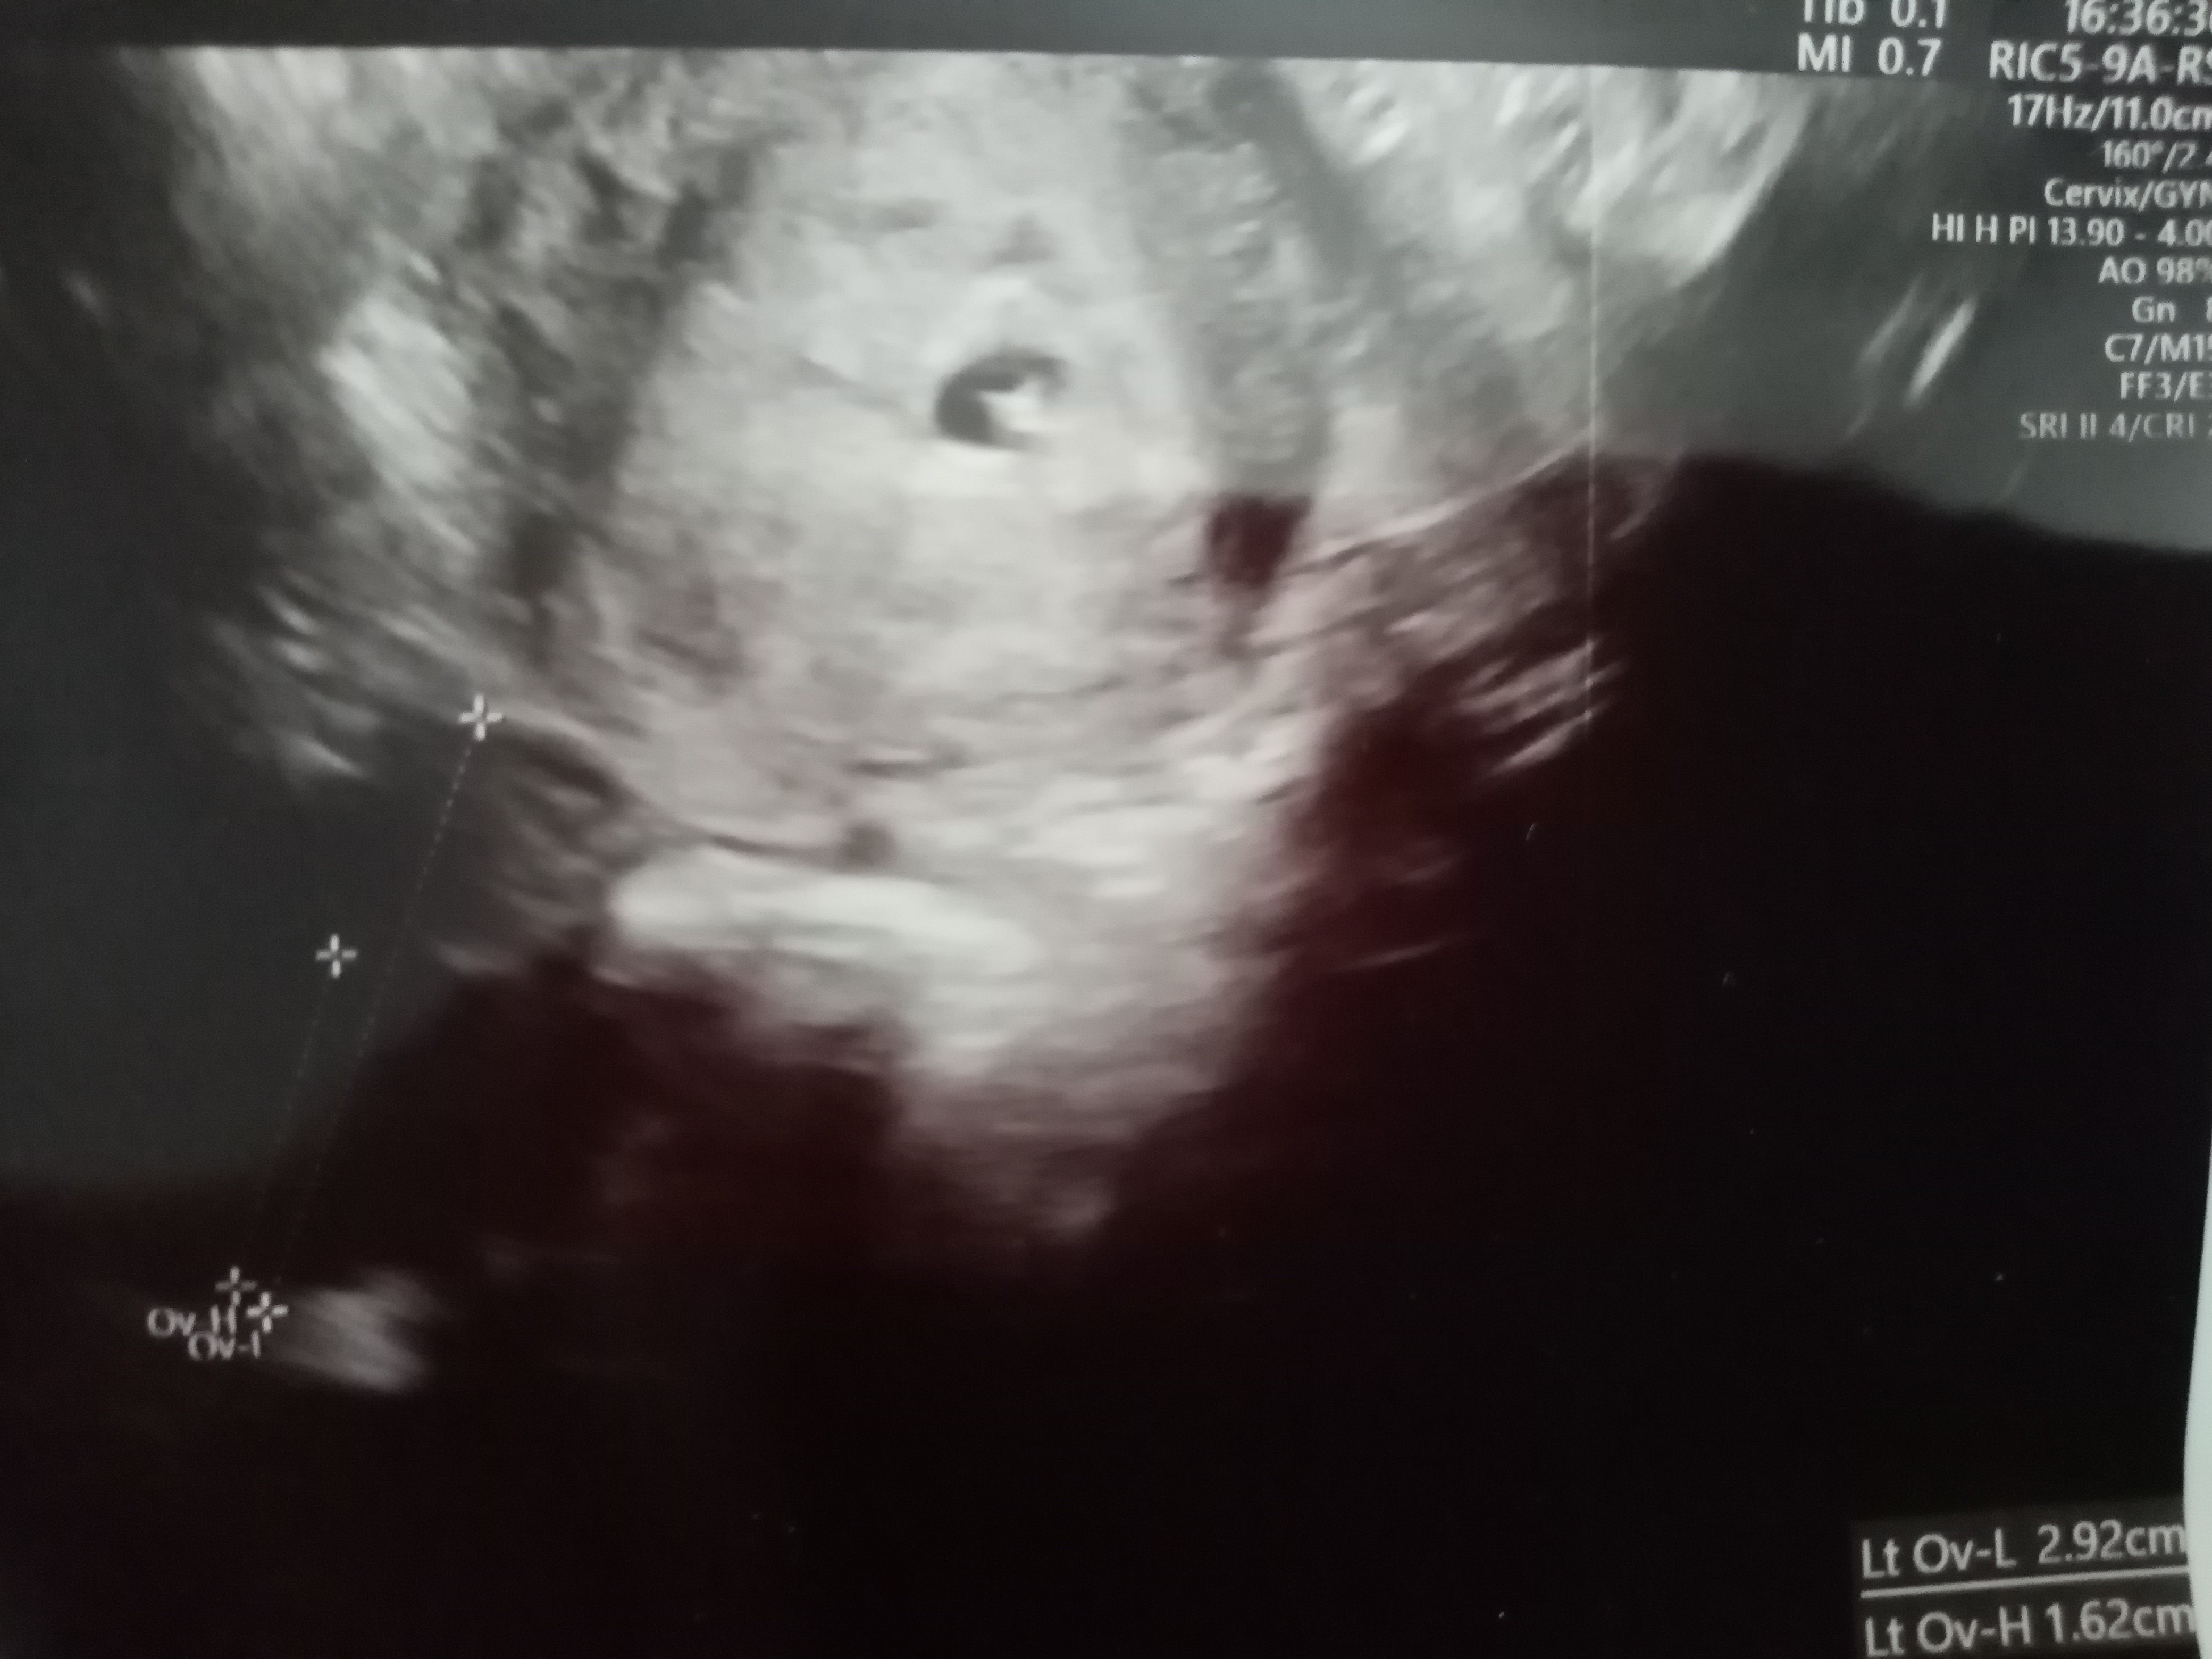

Dziewczyny byłam dzisiaj prywatnie na wizycie. Pęcherzyk jest w macicy i większy niż 2 dni temu ale bez ciałka żółtego . Ma 5mm. Jutro wyniki bety i progesteronu. Wklejam zdjęcia. Co sądzicie?

Załączniki

• IMG_20210617_172726.jpg

IMG_20210617_172726.jpg

1,6 MB · Wyświetleń: 91

• IMG_20210617_172703.jpg

IMG_20210617_172703.jpg

1,5 MB · Wyświetleń: 83

• IMG_20210617_172623.jpg

IMG_20210617_172623.jpg

1,2 MB · Wyświetleń: 84